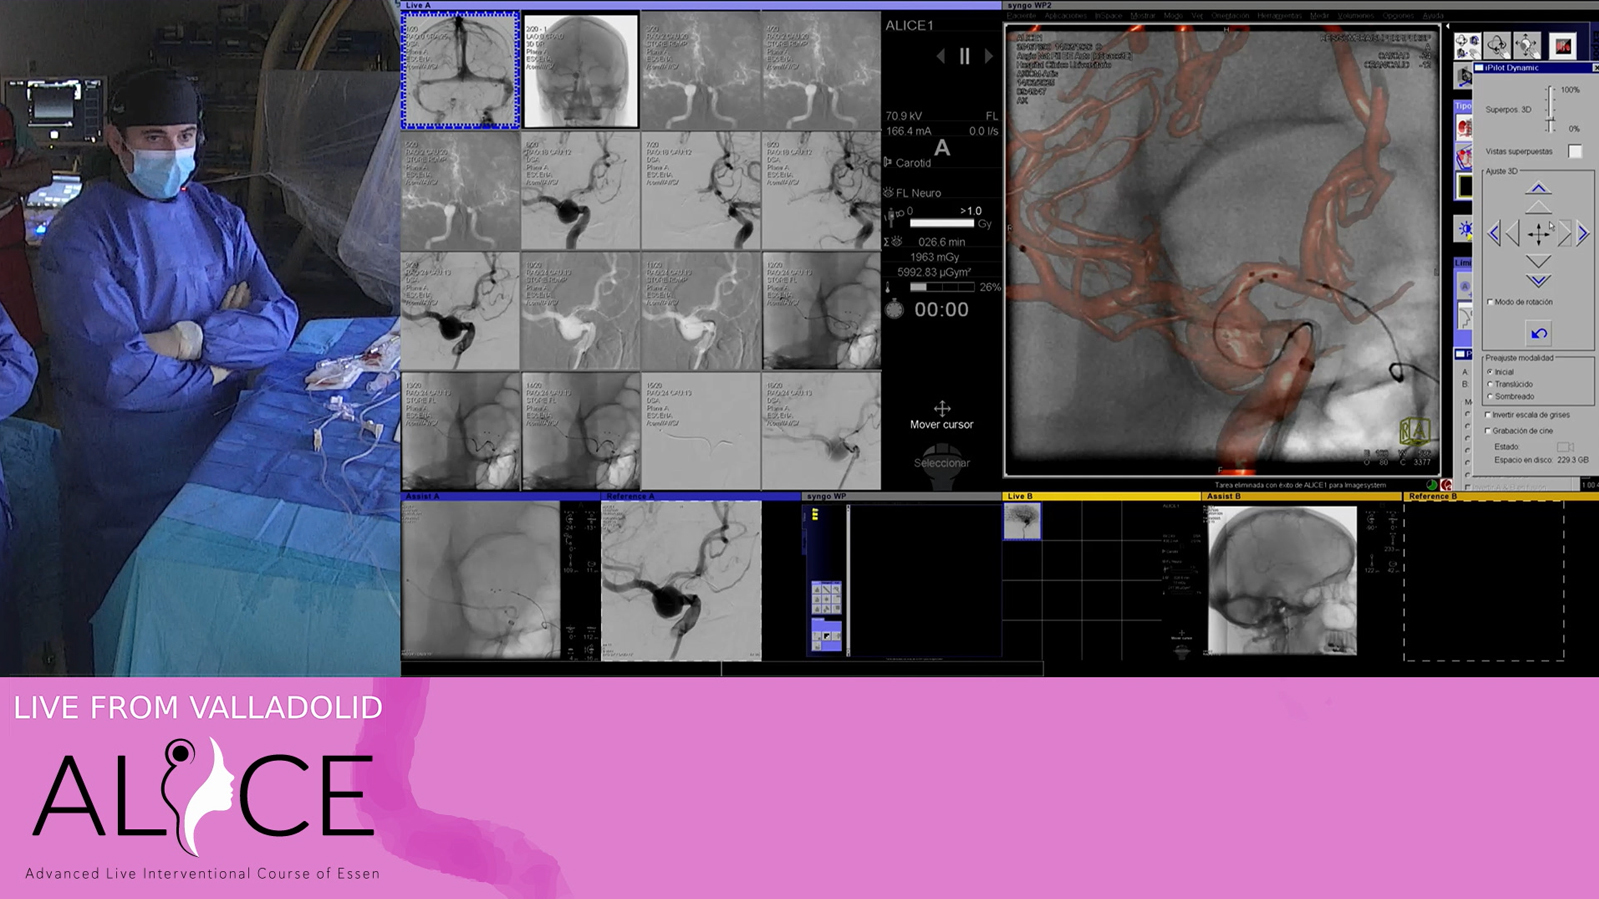

Valladolid: Aneurysm

Fusiform ICA Aneurysm treated by kissing flowdiverter

SCA Aneurysm to be treated by "Chanel" stenting